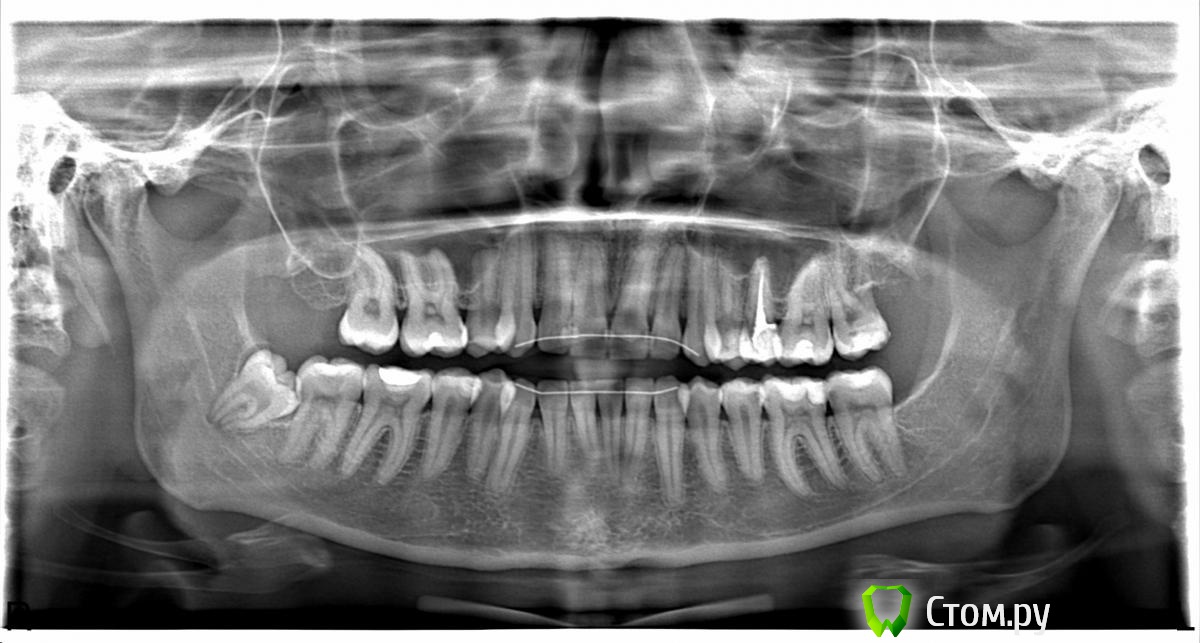

Евгения37 Опубликовано 18 февраля, 2014 Поделиться Опубликовано 18 февраля, 2014 Здравствуйте. В поисках аналогичных симптомов своего заболевания я нашла этот форум и похожую тему Анатолия М. Но у меня ситуация несколько другая. Помогите, пожалуйста, советом.Так сложилось, что проблемы с зубами у меня существуют с самого детства. Все началось, когда мне было 15 лет, с исправления прикуса у ортодонта при помощи брекет-системы, она стояла на верхней и нижней челюсти в течении полутора лет. После было ношение съемной пластинки. В 17 лет мне поставили несъемные ретейнеры на обе челюсти. С того момента прохожу профилактический осмотр в кабинете ортодонта. К стоматологу хожу регулярно, зубы залечиваю во время. Два года назад меня стала беспокоить ноющая боль в левой стороне верхней челюсти. Пошла к стоматологу, мне залечили кариес на 5 и 6. На 5 был глубокий кариес, нерв удалили, запломбировали каналы. Боль не прекратилась и перешла еще и на нижнюю челюсть.Сделали рентген, стоматолог решила, что дело в непрорезавшихся 8-х. Пошла к ортодонту, она также дала рекомендации по удалению левых 8-к. Операция была под общим наркозом 1.5 года назад, в лунки во время операции был вложен препарат Колапан. Назначены антибиотики, полоскание содой и корой дуба, а также УВЧ.Боль какое-то время не беспокоила совсем, если не считать послеоперационного восстановления. Осложнений после операции не было обнаружено.Через месяца 3 боль появилась снова, стала чаще и неприятнее, но терпимее. Обезболивающих я не принимала. Опять пошла к стоматологу, она обнаружила глубокий скол эмали на верхней 7, его повредили, когда отделяли 8. Залечили. Боль не прошла. Стоматолог говорит, что все зубы залечены, не знает в чем дело. Отправила к другому стоматологу.На данный момент боль отдает в висок и доходит почти до лимфоузла (он не увеличен). Проявляется слабо, ноюще, регулярно с утра, днем и к вечеру. Щелчков не наблюдаю, открывается рот как и до операции. Ночью сплю нормально. Стараюсь не есть на левой стороне и не спать. Собираюсь идти к хирургу и нервологу. Прилагаю снимок. Ссылка на комментарий

shishok Опубликовано 18 февраля, 2014 Поделиться Опубликовано 18 февраля, 2014 По снимку очень близко нерв в 27 зубе(верхняя левая семёрка),в первую очередь проверить его+вероятно кариес на передней поверхности 37 и задней поверхности 35.И удаляйте 48! Ссылка на комментарий